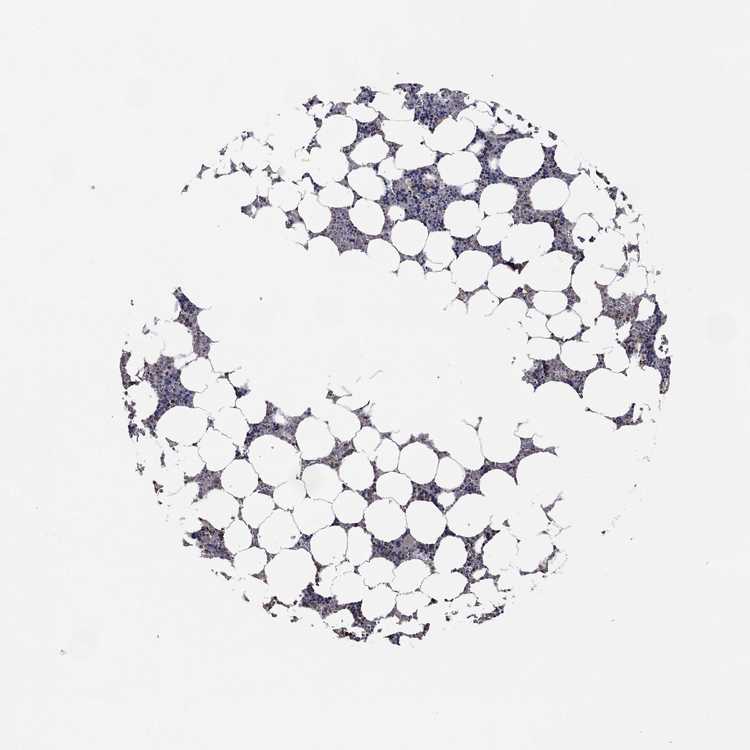

BONE MARROW - Antibody stainingi

Antibody staining in the annotated cell types in the current human tissue is reported as not detected, low, medium, or high, based on conventional immunohistochemistry profiling in selected tissues. This score is based on the combination of the staining intensity and fraction of stained cells.

Each image is clickable and will lead to virtual microscopy that enables deeper exploration of all samples and also displays staining intensity scores, fraction scores and subcellular localization as well as patient and tissue information for each sample.

Antibody HPA071736

Hematopoietic cells Medium